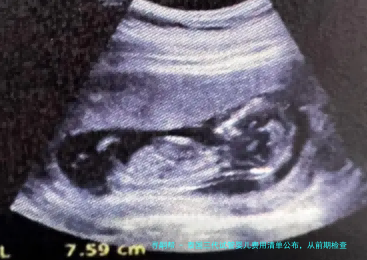

女性检查项目通常囊括:性激素六个项目(评估卵巢功能)、AMH(抗缪勒管激素,卵巢储备)、阴道B超(检查子宫、卵巢模样)、甲状腺功能、感染病筛查、染色体核型分析等。这一些检查的总花销大约在5000-8000人民币。

当卵泡发育成熟后,医生会安排促排卵手术。促排卵手术通常在静脉麻醉下进行,通过阴道B超引导,将卵子从卵巢中取出;男性会在促排卵当天进行取精。促排卵和取精的手术费用,加之实验室的体外受精(试管婴儿)和卵细胞质内单精子注射(ICSI)费用,大约在25000-40000元钱。三代试管婴儿(PGT/PGS/PGD)的核心技术在于胚胎植入前的基因诊断或筛查,这部分费用会额定较量争论。